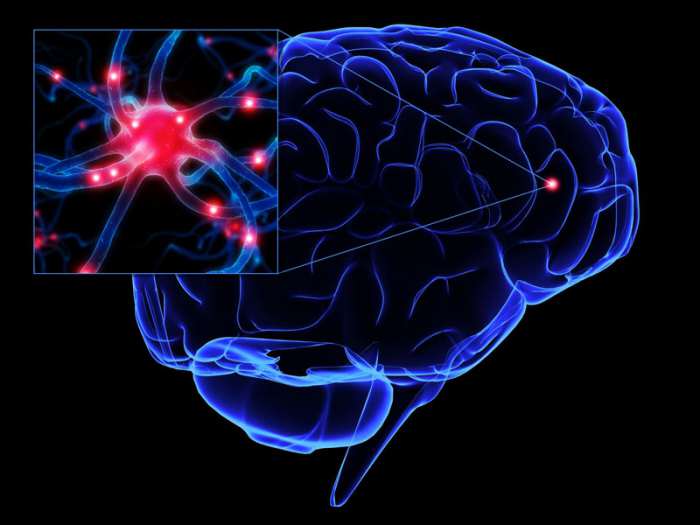

При БАС нервові клітини, що контролюють м’язову активність, поступово відмирають, викликаючи прогресуючу м’язову слабкість, який не піддається лікуванню.

Утруднення дихання – найпоширеніше ускладнення при синдромі Лу Геріга. Хвороба (фото нормального і ураженого нейронів розташоване нижче) з часом паралізує м’язи, відповідальні за поглинання кисню і позбавлення від вуглекислого газу. Існують прилади, що полегшують дихання в нічний час доби. За будовою вони схожі на обладнання, що застосовується людьми з синдромом обструктивного апное. Наприклад, лікар може призначити неінвазивну вентиляцію легень з позитивним тиском, щоб пацієнт зміг нормально спати вночі.